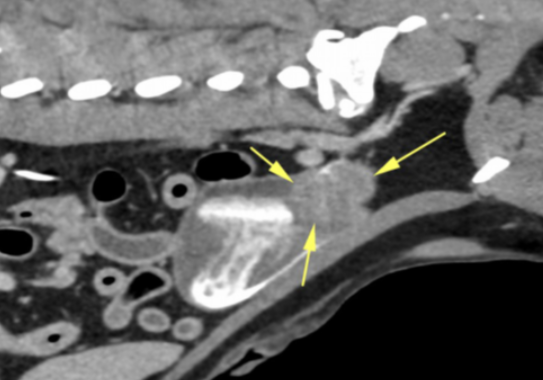

There was an approximately 4cm soft tissue mass located in the bladder trigone (Images 1 – 2). The mass dislocated the right ureter abaxially and dorsally, but was not causing obstruction. There was a large, approximately 7cm x 7cm x2cm parietal mass in the cranial wall of the gastric fundus. The mass protruded into the gastric lumen and was accompanied by an alteration of gastric wall layering (Image 3). A smaller mass was identified in the wall of the greater curvature of the stomach, measuring approximately 4cm x 1cm. The cranial abdominal lymph nodes were enlarged and hypoattenuating (Image 4). No other abnormalities were seen.

Image 2: Sagittal slice of a post-contrast scan showing a mass in the bladder trigone (arrows).